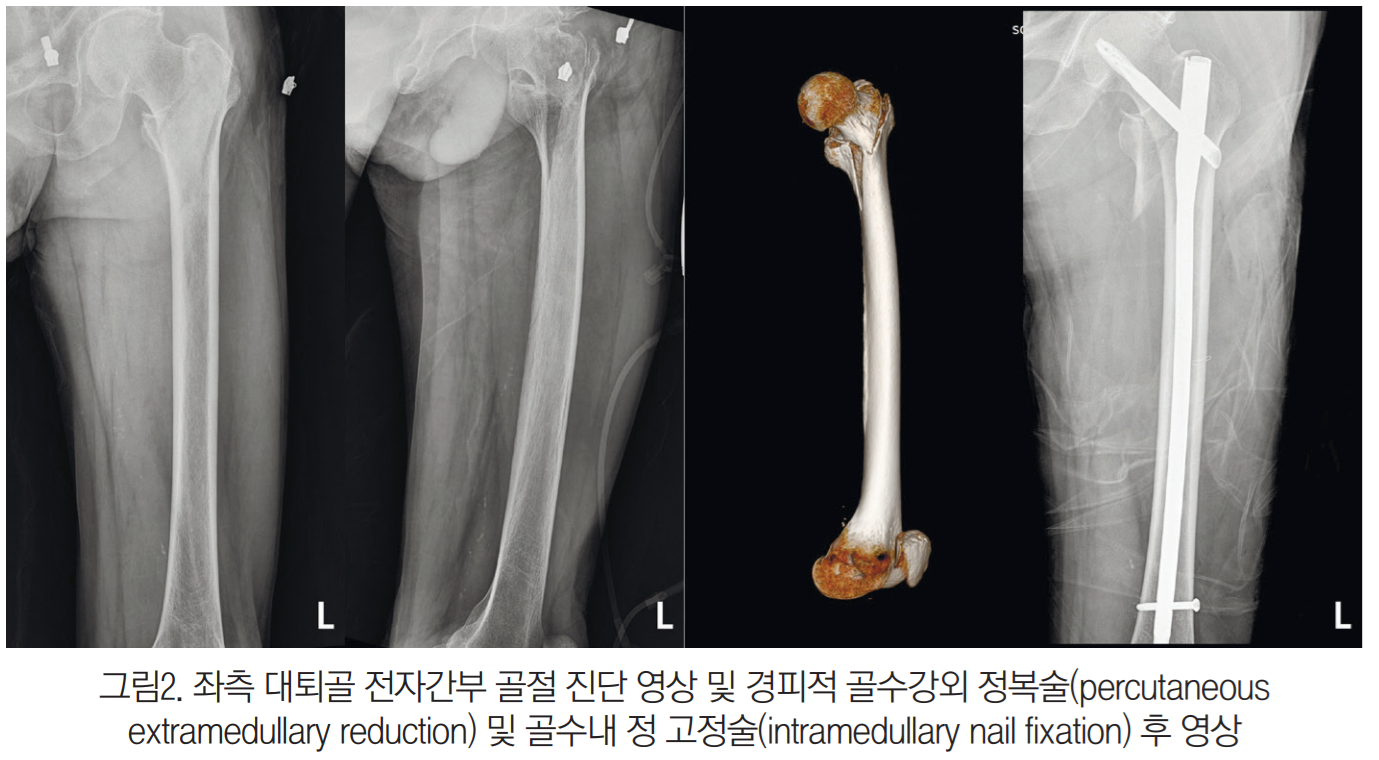

환자의 아버지는 좌측 대퇴골 골절로 진단 후 수술 받았다. 그런데 며칠 전, 추적관찰을 위해 대학병원에 갔더니 정형외과에서 못고정술 시행된 부위가 잘 낫지 않는다, 뼈가 생겨야 하는데 오히려 흡수되고 있다고 했다.

그리고 좌측 대퇴골 전자간부 골절로 경피적 골수강외 정복술 및 골수내 정 고정술을 받았다(그림2). 경동맥 초음파 검사에서는 좌측 근위부 내경동맥에서 중등도 협착, 우측에서는 경도 협착이 확인됐다(그림3).